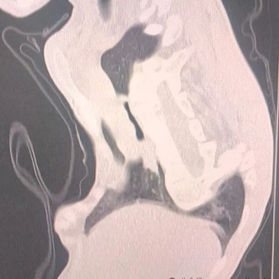

Preoperative Examination

The anterior chest wall exhibited severe complex deformities, manifesting as an overall depression but protrusions at the sternal manubrium and xiphoid process. The lower portion of the chest wall showed an irregular, uneven surface. The heart was significantly compressed, with an oxygen saturation of only 75% without supplemental oxygen. Severe scoliosis was also present.